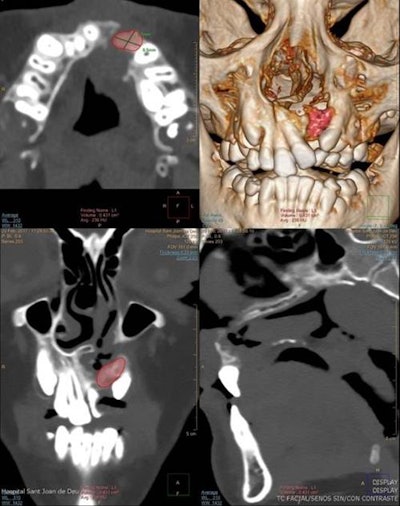

An 8-year-old girl with unilateral cleft lip and palate. Planar measurement (axial) and volumetric measurement before the alveolar bone graft (volume: 1.43 cc3).In the four- to six-month follow-up after alveolar bone grafting, the outcome checklist comprises assessment of bone bridge development (osseointegration), measurement of the bone volume of the graft on 3D CT, checking for the presence of oronasal fistula, and evaluation of facial symmetry. Reabsorption of the bone graft occurs mainly during the first postoperative three months and is closely related to long-term outcome, while normal resorption after one year can be up to 30% to 50% of the original graft volume.

Same 8-year-old girl. Planar measurement (axial) and volumetric measurement after the alveolar bone graft (volume: 0.72cc3).When evaluating bone grafts with 3D CT, bone loss is more prominent in the bucco-palatine direction, and if resorption is higher than 50% or there is lack of normal eruption of adjacent teeth, graft failure should be suspected, according to Gómez-Chiari. Facial symmetry can be assessed by measuring the height from the pyriform aperture to the apex of the upper incisor in a coronal plane.